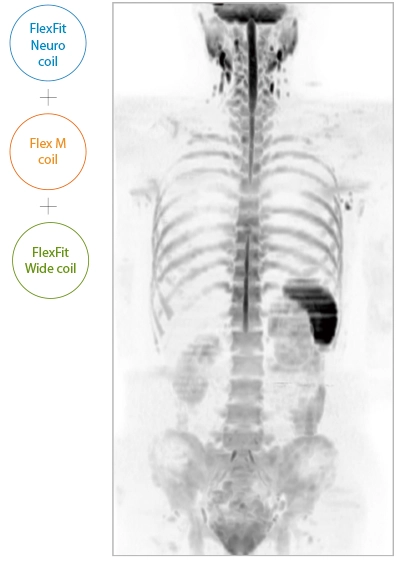

IP-RAPID x DLR Plus can be used for basic imaging such as VolumeScan, RadialScan, HalfScan, and many other imaging methods such as MultiContrastScan FatSep and DWI.

It can also be used with time-consuming scans such as Whole Body DWI and Whole Spine imaging, providing more detailed information in many areas than previously possible.

The ECHELON Synergy ZeroHelium is equipped with a flexible head and neck coil that allows one-action setup via sliding installation, as well as a Flex coil that provides wide and flexible coverage of the imaging area. This enables flexible adaptation to different part of body.